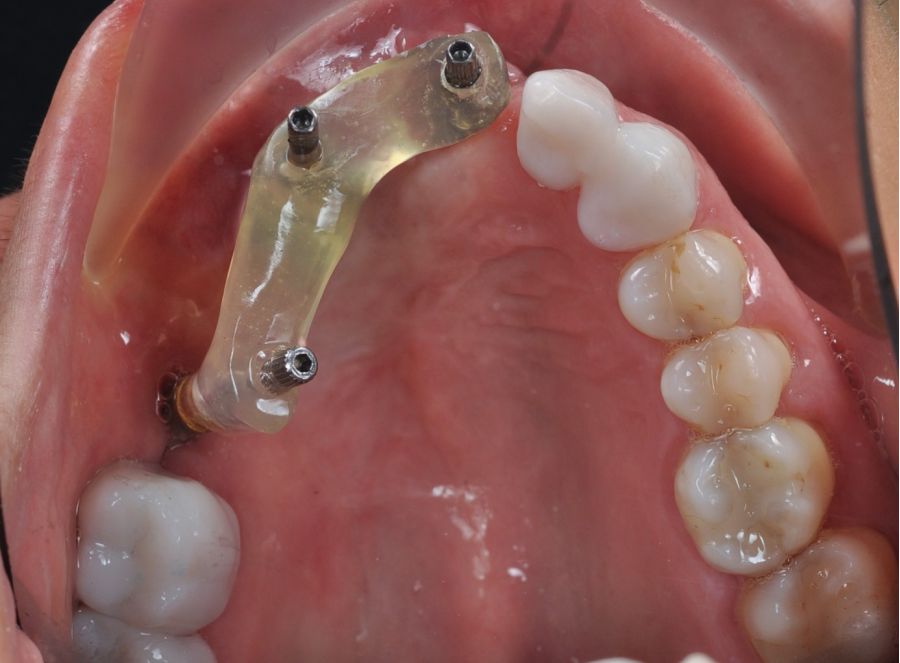

Una vez finalizada la radioterapia, la paciente se encontraba libre de enfermedad. Por lo que se procedió a la restauración definitiva implantosoportada. Tras la segunda fase, se colocaron dos pilares transepiteliales Multiunit Ò rectos y un pilar Multunit Ò angulado de 17º (Figura 10).

Para la fabricación de las estructuras, se eligió el óxido de zirconio monolítico como material restaurador sobre interfases metálicas en el puente implantosoportado, y coronas de óxido de zirconio monolítico en los dientes tallados previamente (1.7, 1.6, 2.2 y 2.3). Se tomaron impresiones de cubeta abierta con silicona de adición pesada y fluida (Zhermack Elite HD, Gmbh). Se realizó una prueba de pasividad analógica y el resto del proceso se confeccionó de manera digital, por lo que se hicieron pruebas estéticas de dientes impresas en 3D sobre interfases metálicas, para hacer todos los ajustes de función y estética previos al fresado del zirconio monolítico (Figuras 11, 12 y 13).

Finalizado el tratamiento oncológico y confirmada la ausencia de enfermedad activa, se procedió a la segunda fase quirúrgica con la colocación de pilares transepiteliales Multiunit®. La integración de los implantes cigomáticos y del implante endoóseo fue satisfactoria, observándose estabilidad clínica y ausencia de signos de periimplantitis.

Las impresiones analógicas y el posterior flujo digital permitieron una correcta planificación protésica. Las estructuras definitivas, confeccionadas en óxido de zirconio monolítico sobre interfases metálicas de titanio, mostraron una adecuada adaptación pasiva tanto clínica como radiográficamente. La prueba estética permitió ajustes oclusales y funcionales mínimos, optimizando el resultado final.